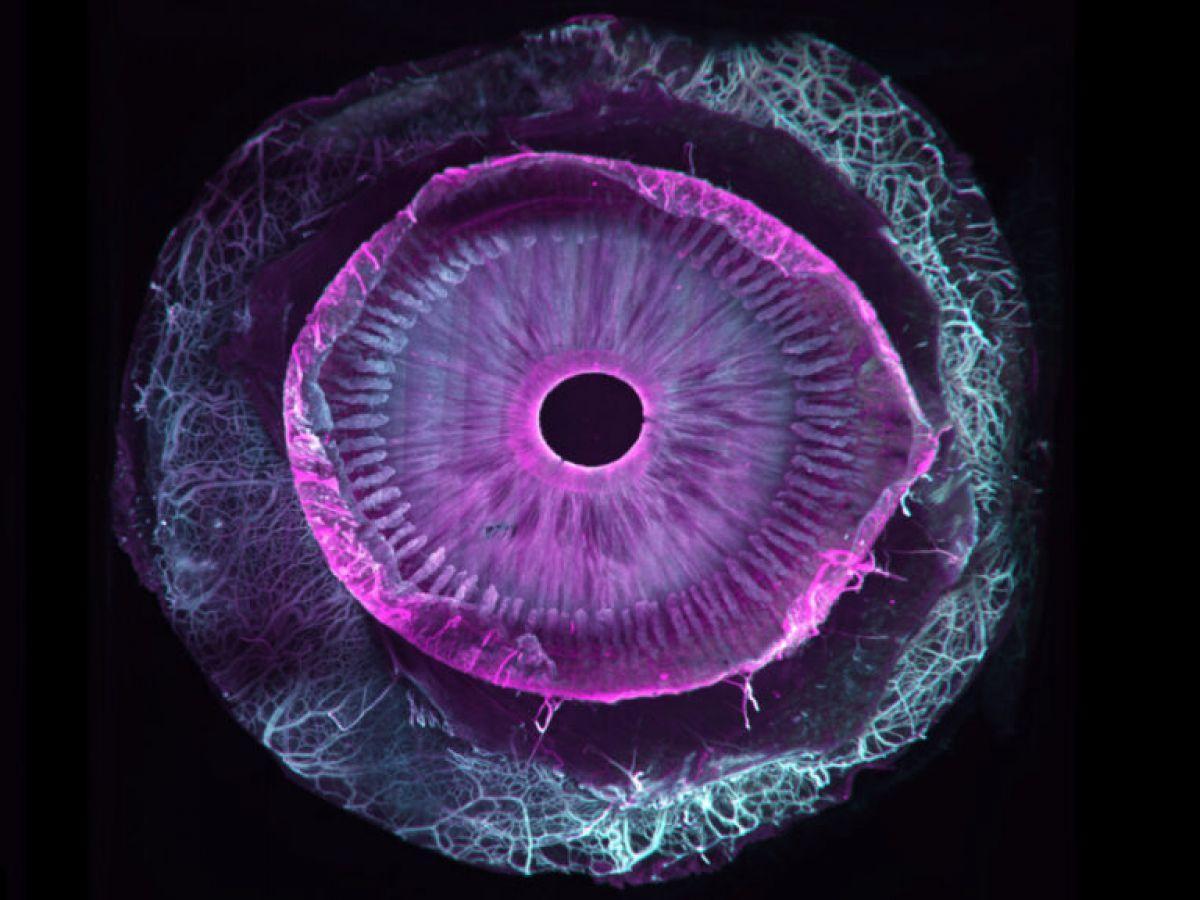

Africa-Press – Togo. Sept ans de travail pour une première mondiale : la transparisation (le fait de rendre transparent) d’un œil humain entier. Ce travail, tout juste publié dans la revue Communications Biology, est une collaboration franco-suisse entre, d’une part, Marie Darche, une ingénieure de recherche et membre de l’équipe du Pr Michel Paques à l’hôpital des Quinze-Vingts et à l’institut de la vision (Paris), et d’autre part ses collègues de l’institut Wyss (Genève).

Si les seconds se sont eux occupé du versant imagerie du projet grâce à un dispositif optique particulier, un microscope à feuillet de lumière (MesoSPIM), la biologiste s’est, elle, attaquée au versant « clearing », c’est-à-dire les étapes de transparisation permettant de transformer un échantillon biologique initialement opaque en une structure transparente. Comment ? Par différentes manipulations reposant sur une succession de bains dans des solvants organiques associées au marquage par des anticorps fluorescents.

Tout commence forcément avec des dons d’yeux, issus ici de donneurs américains morts, la législation française ne permettant pas ce type précis de dons (la banque française des yeux ne s’occupe que des cornées et pas d’œil entier). En pratique, toujours de petites sphères de six centimètres cube de volume, dont on ne soupçonne pas l’extraordinaire complexité ni l’hétérogénéité en lien avec les différentes couches de cellules, vaisseaux, nerfs, cellules immunitaires…

Car si d’autres équipes étaient parvenues par le passé à clarifier certains segments de l’œil, c’est bien ici la première fois qu’un œil entier est transparisé. « Au total, nous avons utilisé 25 yeux sains et allons prolonger nos travaux avec d’autres globes oculaires cette fois pathologiques et atteints de DMLA (dégénérescence maculaire liée à l’âge, ndlr), de glaucome et de myopie forte, le tout grâce au soutien d’associations de patients », précise la chercheuse, qui poursuit : « Nos travaux permettront une approche plus holistique des pathologies de l’œil tout comme un meilleur dialogue entre chercheurs et cliniciens pour mieux comprendre les maladies de l’œil et leurs mécanismes ».